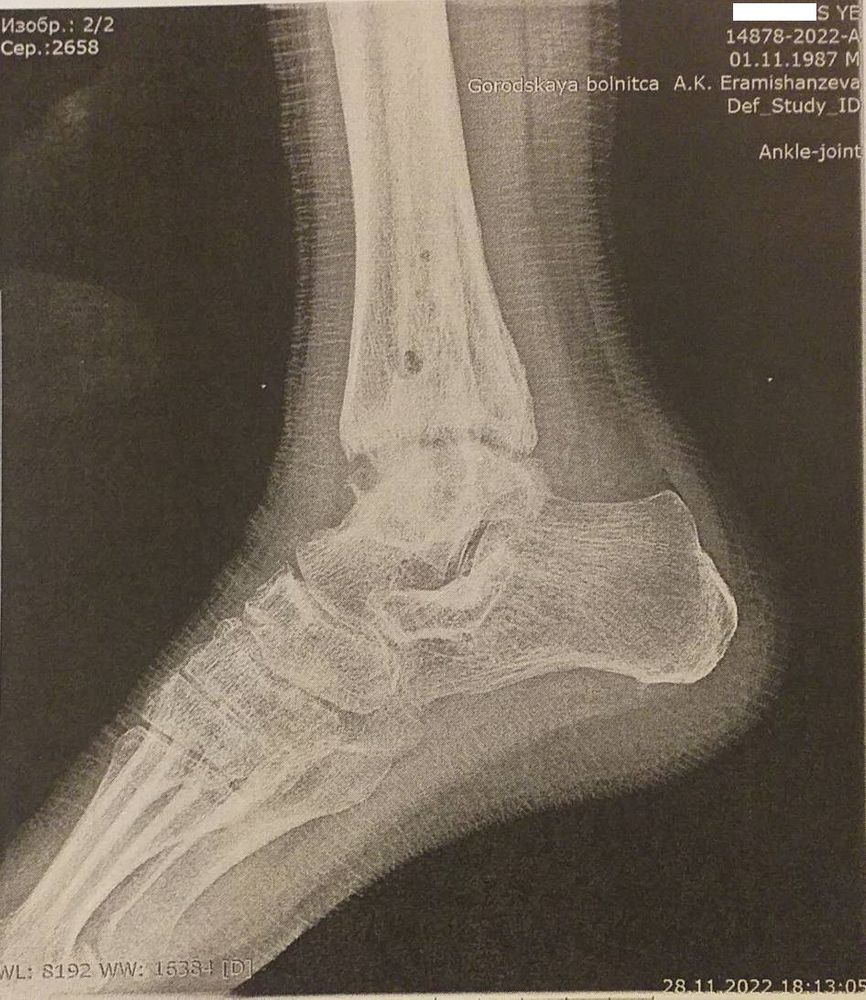

Всем приветы! Сделала сегодня перед операцией КТ голеностопного сустава. Вот что пишут: Изображение

С495, Приветы! Сделала сегодня перед операцией КТ голеностопного сустава. Вот что пишут: Изображение

Dari, Всем приветы! Сделала сегодня перед операцией КТ голеностопного сустава. Вот что пишут: Изображение

И, Приветы! Сделала сегодня перед операцией КТ голеностопного сустава. Вот что пишут: Изображение

oxana(vogel), Всем приветы! Сделала сегодня перед операцией КТ голеностопного сустава. Вот что пишут: Изображение

Тати, Всем приветы! Сделала сегодня перед операцией КТ голеностопного сустава. Вот что пишут: Изображение